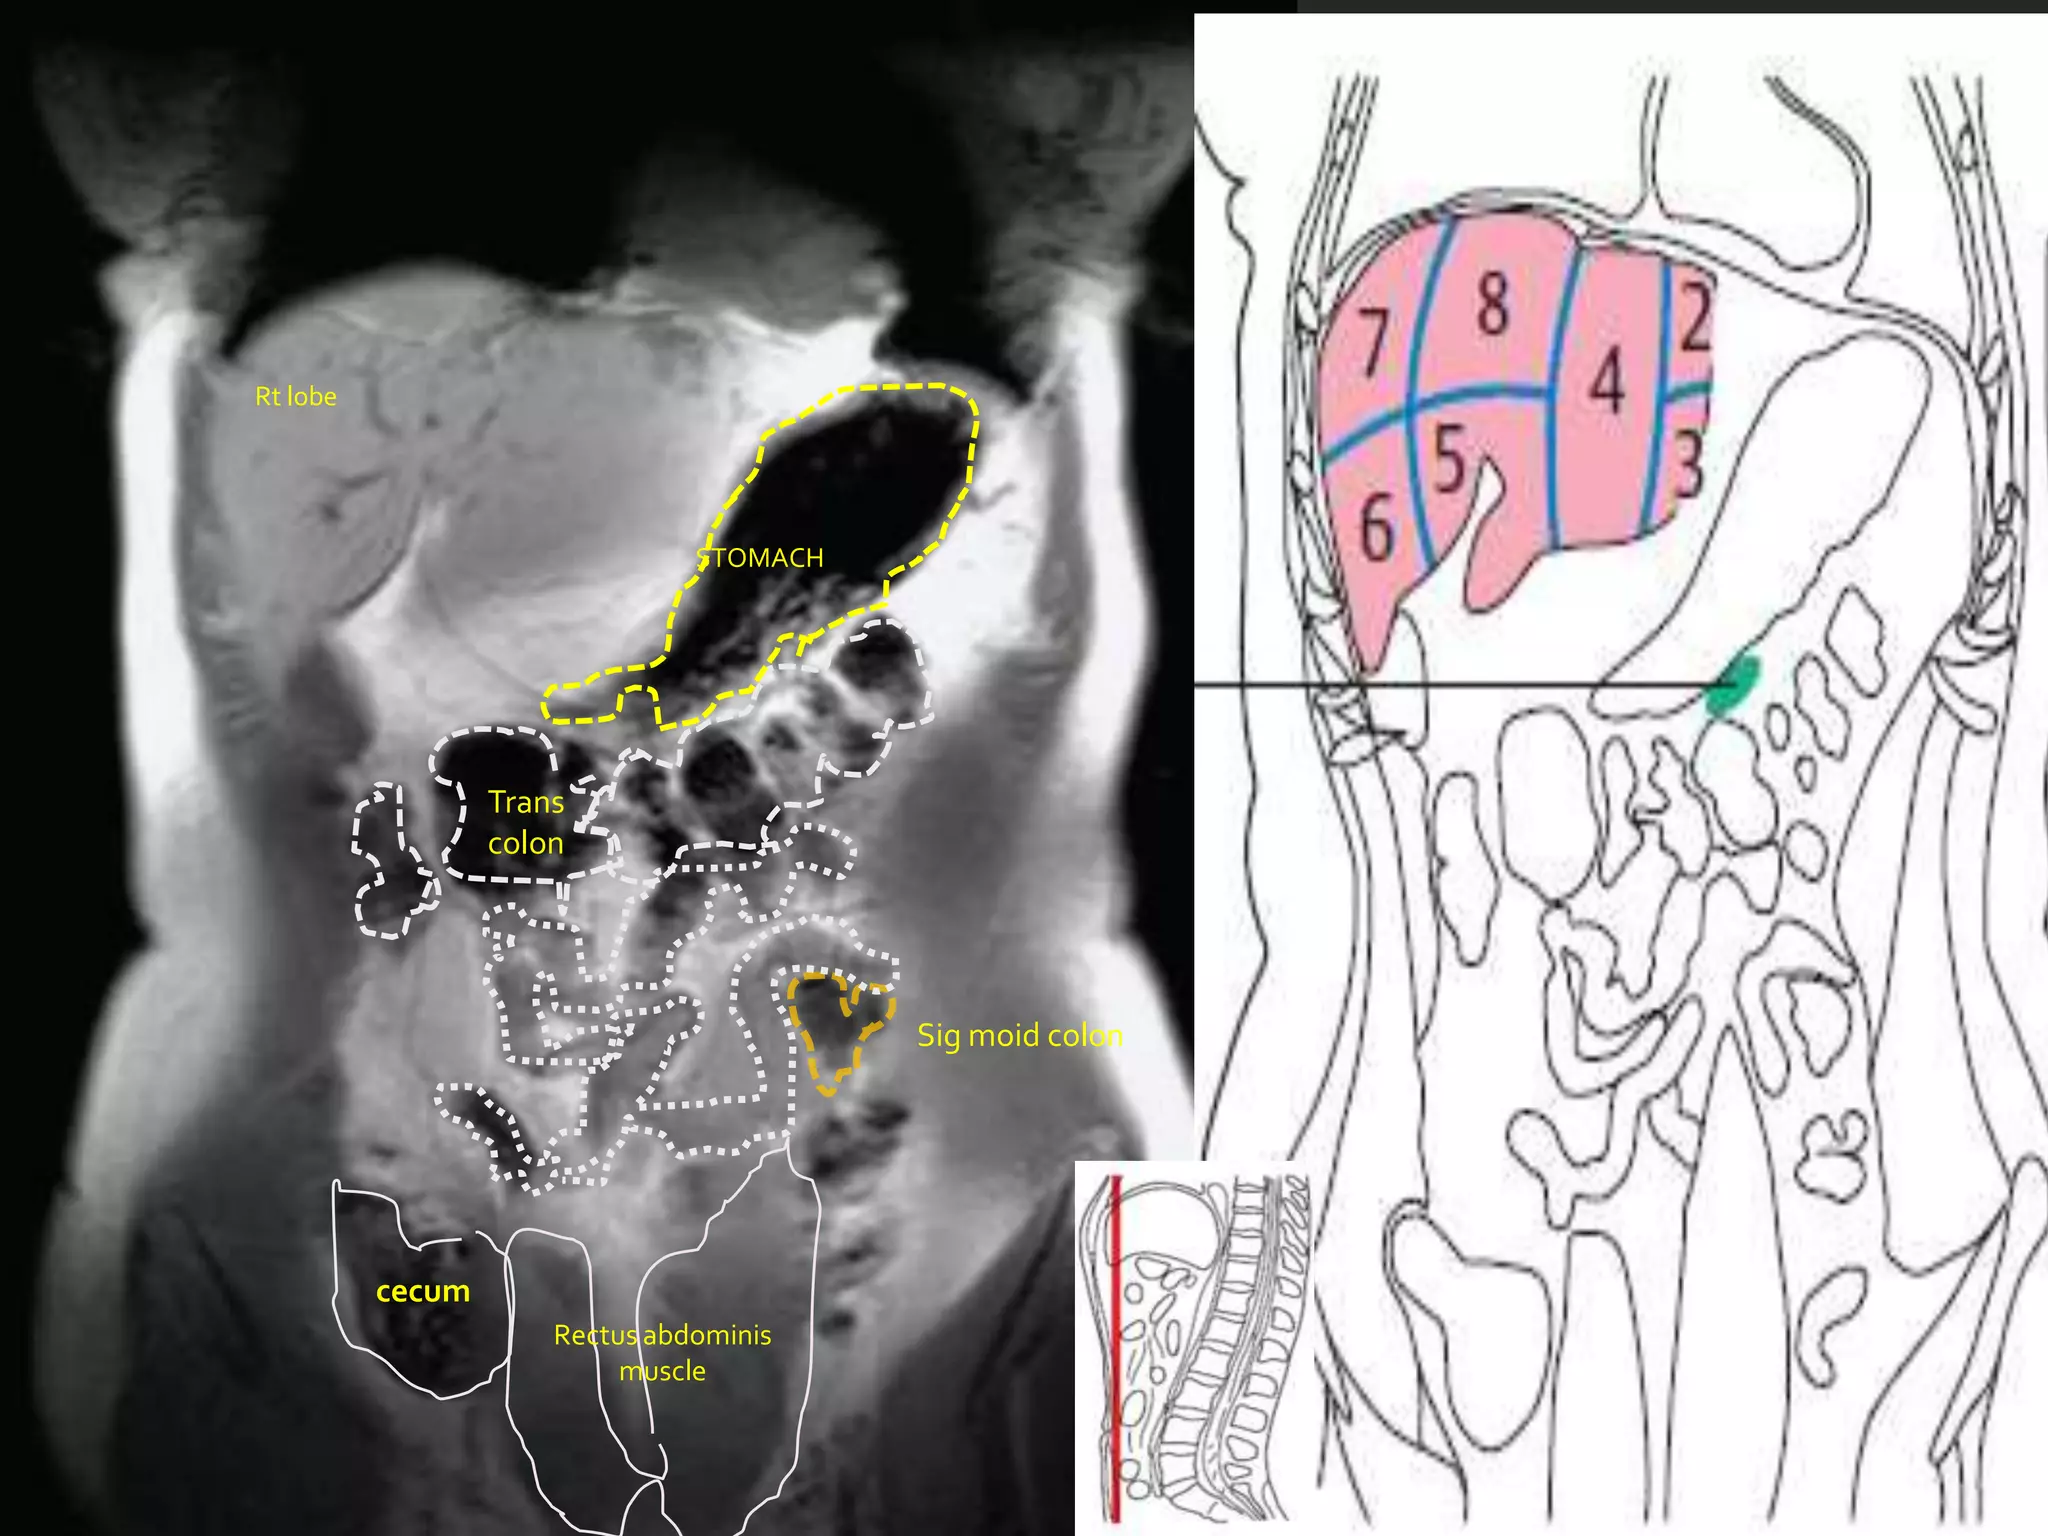

Rt lobe

STOMACH

Trans

colon

Sig moid colon

cecum

Rectus abdominis

muscle